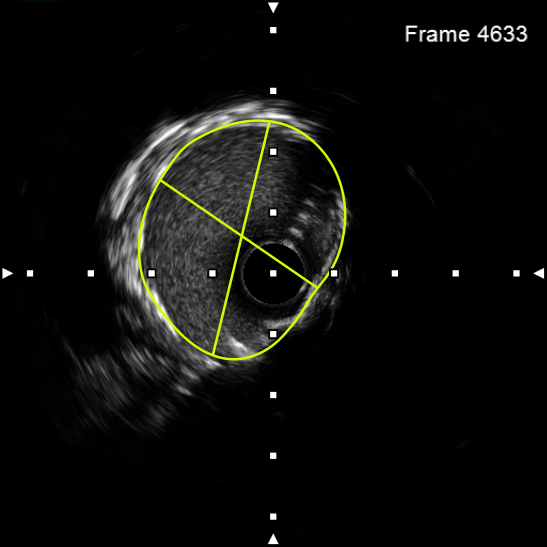

图3 IVUS示右冠中段支架膨胀不良,支架内多处可见新生钙化病变

该患者入院后,完善相关检查并再次建议行CABG治疗,但家属仍拒绝,遂考虑再次行PCI手术干预。冠脉造影提示患者冠脉右冠状动脉中段70-95%再狭窄,左主干末端80%狭窄,前降支原支架中远段 80-95%再狭窄,回旋支完全闭塞,急需手术尽快解决冠脉血流灌注问题,否则随时有生命风险,但患者多处支架内/节段内再狭窄,造影提示钙化明显,外院已尝试无法扩张,经手术团队充分讨论后,计划在IABP支持下,先进行右冠状动脉干预,利用IVUS精准评估原支架再狭窄部位情况,采用旋磨或Shockwave冲击波球囊处理无法扩张的病变部位,右冠处理后择期进行左冠状动脉干预。在制定了详尽的手术计划后,手术团队首先对患者的右冠状动脉行IVUS检查,结果提示该患者右冠中段支架局部膨胀不良,局部支架面积6.67mm²,管腔内多处可见钙化小结及270°以上钙化,IVUS钙化积分达3分。由于膨胀不良处原支架后方可见钙化斑块,常规旋磨效果不佳,对于此类钙化病变,IVL处理是最佳方案。手术团队对近端采取棘突球囊及高压球囊进行扩张,采用Guidezilla辅助下输送3.0mmx12mm Shockwave冲击波球囊于右冠钙化处进行冲击波钙化斑块碎裂术,通过IVUS证实支架内的新生钙化病变得到松解,原膨胀不良部位支架面积达到7.76mm²,后经过高压球囊充分预处理,顺利完成右冠支架植入,术后复查右冠原膨胀不良部位支架面积9.17mm²。